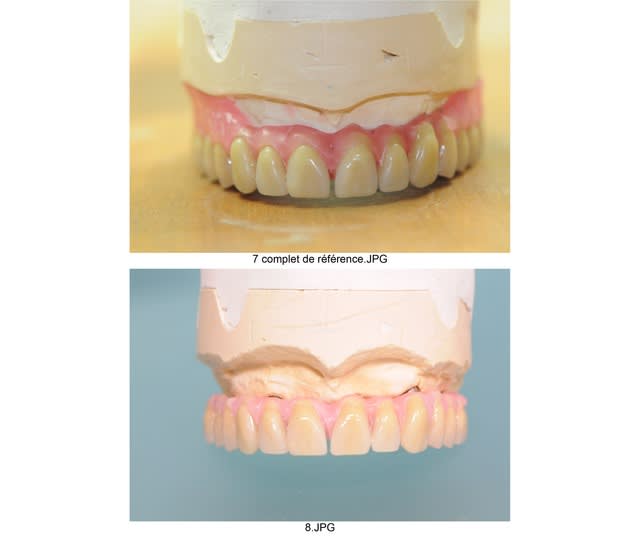

comme on apprends beaucoup de ses erreurs mais aussi un petit peu de celles des autres, je t'envoie justement les photos de mon premier all on 6 .

tu trouvera sans difficultés où j'ai merdé à l'époque.